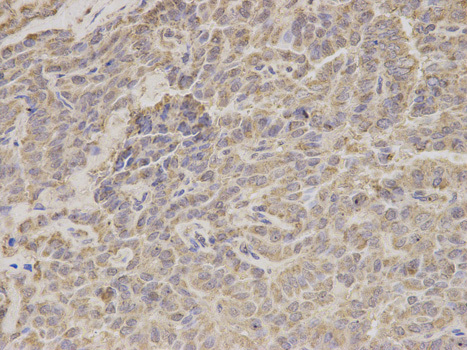

Supportive validation

- Submitted by

- OriGene (provider)

- Main image

- Experimental details

- Immunohistochemical of paraffin-embedded human thyroid cancer using HADHA antibody at dilution of 1:200 (400x lens).

- Validation comment

- IHC